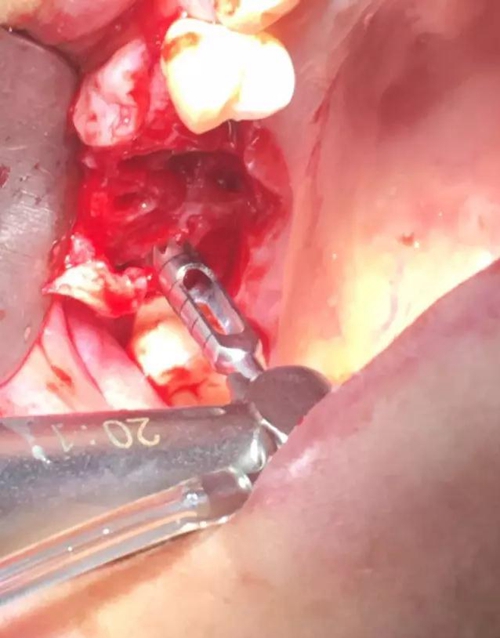

【病例分享】?jī)?nèi)提,用自體骨柱,不用骨粉

4.jpg